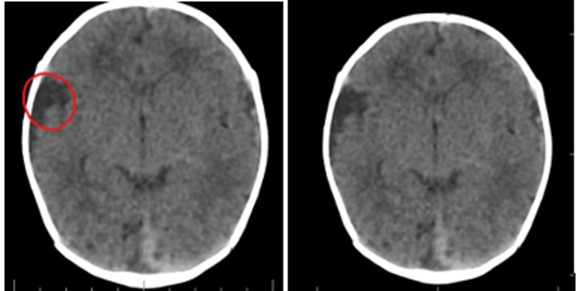

Por lesión dermoide consideraron que el paciente cursaba con aplasia cutis y en conjunto con las demás alteraciones estructurales del ojo y hemicara derecha (quiste dermoide escleral, coloboma y microtia) realizaron diagnóstico de síndrome de Goldenhar. Con la intención de descartar otras malformaciones asociadas, solicitaron tomografía axial computarizada (TAC) de cráneo que reportó quiste aracnoideo en la fosa temporal derecha y mega cisterna magna como variante anatómica (ver imagen 4). La TAC de columna cervical, ecocardiografía y ecografía de vías urinarias fueron normales.

Figura 4. Tomografía cráneo. Quiste aracnoideo en la fosa temporal derecha y mega cisterna magna como variante anatómica.

En el caso reportado, se sospechó GHS por el conjunto de características clínicas relacionadas, como aplasia cutis, quiste dermoide escleral, coloboma, microtia leve, además, del hallazgo imagenológico de quiste aracnoideo en la fosa temporal derecha y mega cisterna magna como variante anatómica aislada, algunos casos reportados en la literatura describen la presencia de quistes dermoides intracraneales en menor frecuencia de presentación (10).